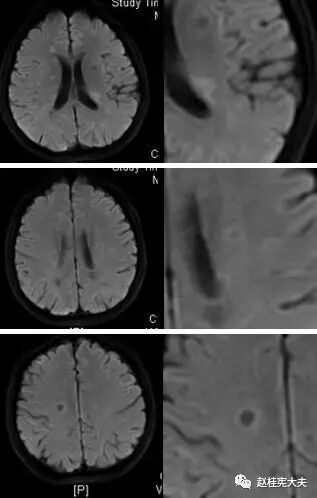

图11. 示双侧半卵圆中心、放射冠区病灶DWI像呈较高信号,以结节边缘较明显。

多发性斑块在MR上表现为多灶性T1WI等或低信号,T2加权图像(FLAIR序列上尤为明显)上特征性不同程度的高信号,可反映脑灰、白质炎症病变;部分病灶在增强图像上表现为局灶性钆对比增强性信号改变,反映局部急性血脑屏障破坏和活动性炎症反应;较大的活动性斑块在DWI上亦可显示弥散受限。

位于脑室周围典型者,长圆形病灶的长轴与大脑或侧脑室长轴垂直,且有一狭窄正常信号带将病灶与侧脑室分开,而之后转为正常表现的低信号提示髓鞘再生;在疾病晚期,病变可发生融合,T2上出现融合性高信号灶,易误为肿瘤;因病灶可沿室管膜静脉从脑室表面进入邻近白质,故胼胝体常首当其冲罹病,且好发于胼胝体内侧或深部,即靠近脑室边缘处。